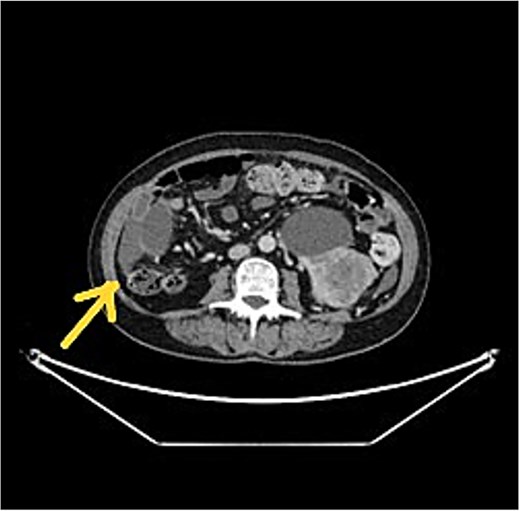

Patients referred with peritoneal malignancy were evaluated in a speciality multidisciplinary team (MDT) meeting with scans reviewed by specialist peritoneal malignancy radiologists (Figs 1 and 2) and experienced peritoneal malignancy surgeons. The standard imaging was dual contrast computed tomography (CT) of the chest, abdomen and pelvis. Tumour marker assessments include CEA, CA19.9, and CA 125. Patients with a renal mass were discussed in a renal cancer MDT.

CT scan showed left RCC, appendix tumour with surrounding mucin.